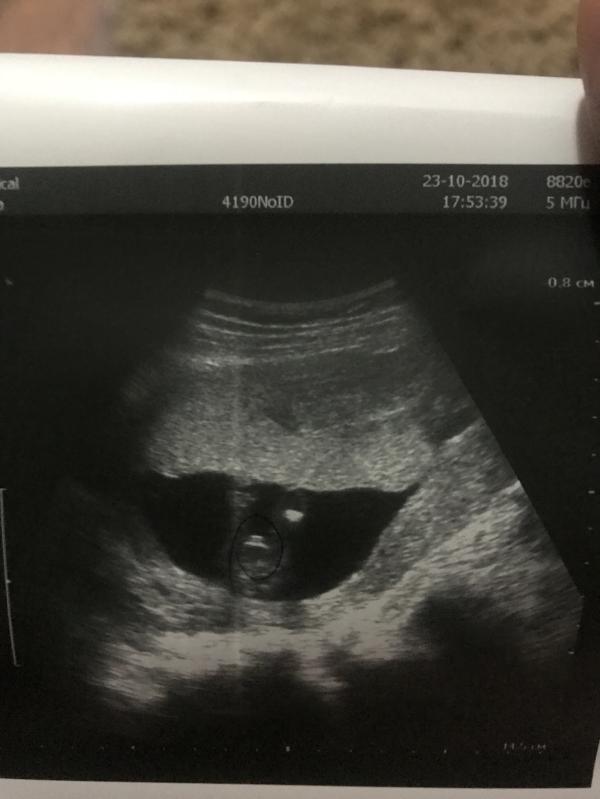

Девочки, сходила я всё-таки на внеплановое УЗИ (ради пола ) и мне стыдно признаться, я расстроилась 😞 ничего не могу поделать с собой, когда она сказал — у вас мальчик, у меня аж сердце замерло, потом она смотрела и все повторялала да да 100 % мальчик, никаких сомнений, вот сами посмотрите… а у меня прям слезы 😞 просто у меня есть сын и я ну очень сильно хотела дочь, я почему-то уверена была что скажут — девочка 😢 мне очень стыдно, я понимаю главное здоровый и я все равно буду его любить, но просто не могу это принято и все!

Срок 15,3 дня, клиника хорошая, платная! И по фото сама вроде виду что мальчик… но все же

.Скажите может было у кого когда говорили на таком сроке мальчик, а родилась девочка? Или это уже 100 % мальчик?